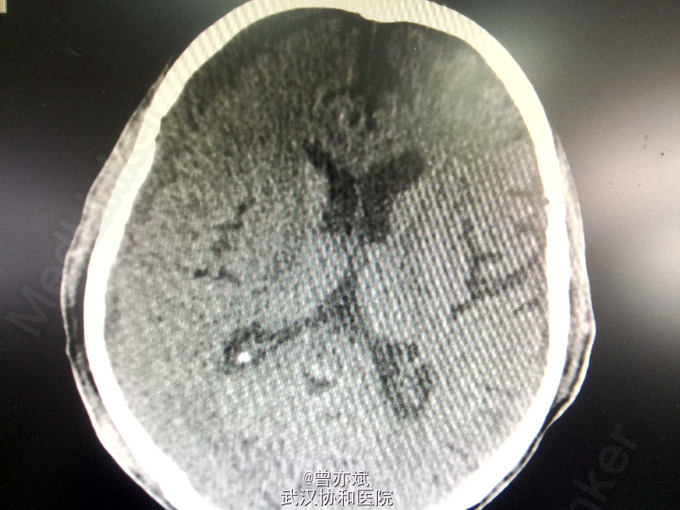

主诉:双下肢乏力3月余,加重1周 现病史:患者2月前意外摔倒后感双下肢乏力,无昏迷、恶心呕吐、头痛头晕等症状,未予特殊处理,今日感双下肢乏力加重,来我院就诊,行CT示右侧慢性硬膜下血肿。

诊断:慢性硬膜下血肿 处理:行微创钻孔引流术